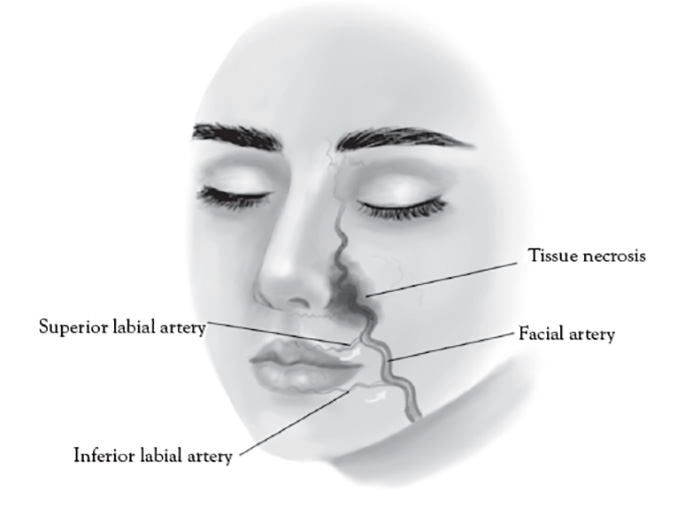

The paranasal area becomes a target in aesthetic practice, particularly with regard to injection of cosmetic fillers in achieving a "liquid rhinoplasty" or nasal contouring (Figure 7).Unlike other areas of cosmetic filler injections, midline nasal injections should be injected deep rather than superficial, because vascularity is more superficial, avoiding nasal bridge and ala [139]. Safe zones include midline middle third and lateral zone between the borders of the lateral nose and nasofacial groove. Avoid superficial injections of the alar tip and alar groove (avoid the crease) [139]. Nasal injection is the leading cause of tissue necrosis (Figure 8) [139,140].

The facial artery is a branch of the external carotid artery, emerging superficial to the posterior belly of the digastric muscle, stylohyoid muscle, and submandibular gland, and coursing in a continuous oblique plane (1.5 cm)from the lateral commissure of the mouth to nasal ala along the lateral border of the nasolabial fold [146]. Proper injection technique for injecting cosmetic filler to the nasolabial fold is medial and very superficial, targeting the lower two-thirds intradermal plane, avoiding the nasal ala, where facial artery is most superficial [147].Inadvertent direct subcutaneous intravascular facial artery injection and/or compressive ischemia in the upper third of the nasolabial fold can result in an ocular embolism, blindness, and necrosis of the alar and malar region of the nose and cheek [148]. The facial artery is visible with color Doppler ultrasound when using proper technique (Figure 9).

The facial artery is located 15 mm lateral to the lip commissure and divides into the superior labial artery in the upper lip and inferior labial artery of the lower lip (Figure 10). These arteries are typically deep and run between the orbicularis oris muscle and oral mucosa [149]. General rules when addressing this facial area are [20,149]: